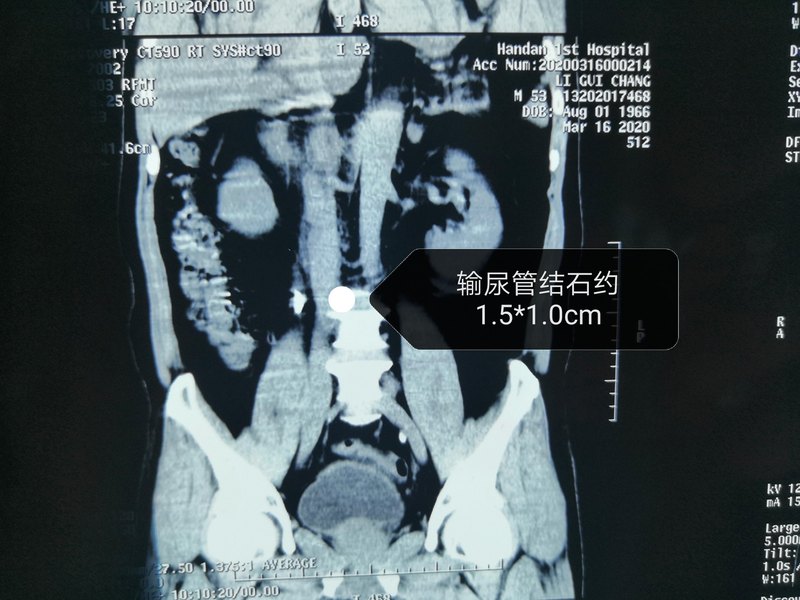

今日手術(shù)分享,男性患者李某,53歲,因“反復(fù)右側(cè)腰痛6個(gè)月”入院,CT顯示:右側(cè)輸尿管上段結(jié)石,約1.5*1.0cm,既往3次體外碎石無效。 今日上午我們?yōu)樗M(jìn)行了輸尿管鏡下鈥激光碎石,徹底清除結(jié)石,解決了患者的大問題。 輸尿管結(jié)石是泌尿外科最常見的疾病之一,嚴(yán)重影響人們的健康。 輸尿管結(jié)石患者通常會(huì)有劇烈腎絞痛,這是因?yàn)榻Y(jié)石阻塞輸尿管,尿液無法排除,腎臟會(huì)憋脹積水,進(jìn)而引起腰部及腹部劇烈疼痛,有時(shí)候會(huì)放射到睪丸及外陰。輸尿管結(jié)石的治療原則是最大限度的去除結(jié)石,恢復(fù)輸尿管腔尿液引流通暢性,緩解腎絞痛,控制尿路感染,保護(hù)腎功能。 對于